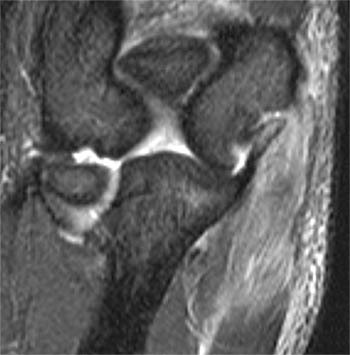

Baker’s cysts are located where

between medial head of gastroc and semimembranosus